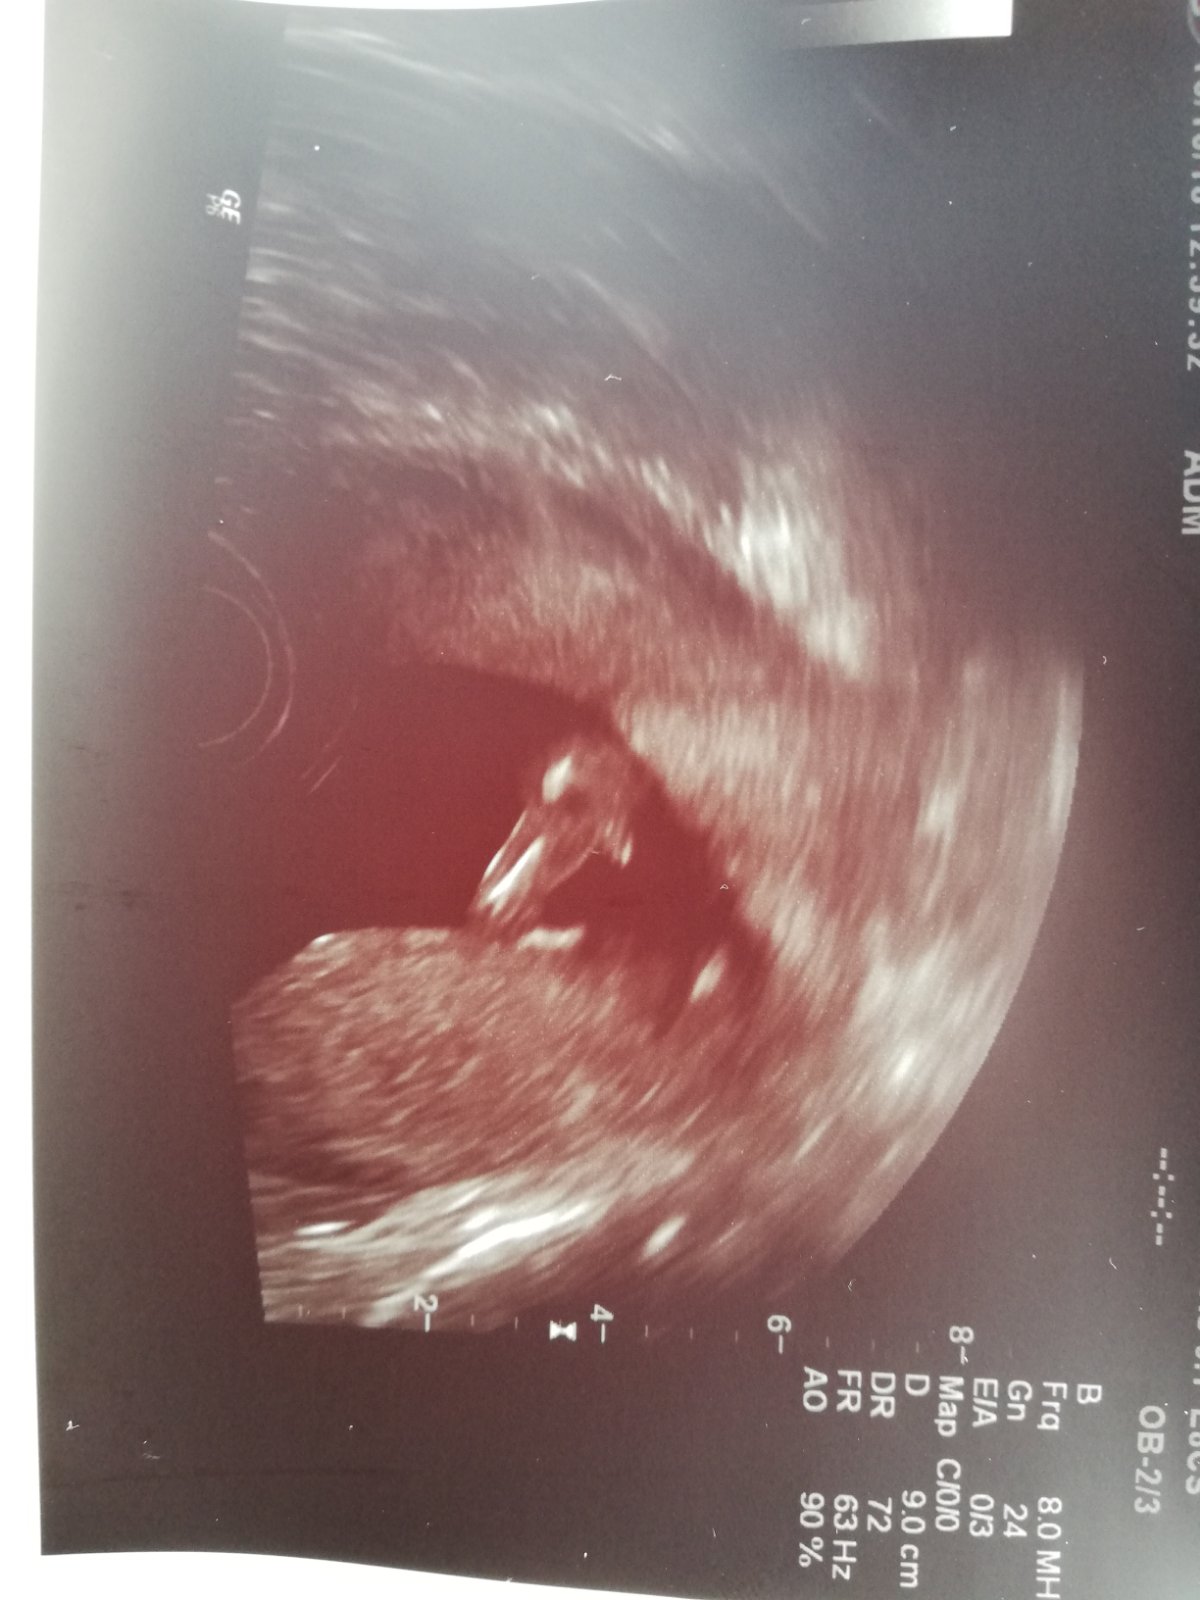

Přikládám foto ultrazvuku holčičky v 16tt pro ostatní maminky pro porovnani, je to zaber zespodu jakoby na prdku s roztazenyma nozkama 😉.

@mrnousek121 no me prave prijde,ze jde celkem rovnobezne s pateri...tak uvidime 😊

@mrnousek121 Nevim právě,co je p.šňůra. Jako hrbolek mi asi přijde taková ta malá bílá vystouplá čárka,ale jistě to nevím.

@kristyna14092013 holčička. pohlavní hrbolek je souběžně s osou páteře. kdydy výrazně čněl nahoru, je to kluk 🙂